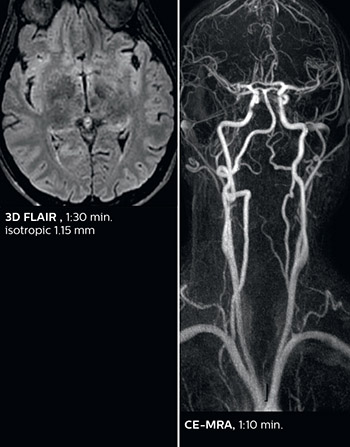

Fast acute stroke protocol

This is an example of acute ischemic stroke with distal occlusion of the right posterior cerebral artery. Note the improved visibility of the ischemic territory on the diffusion weighted image with high b-value. The 3D FLAIR shows a distal PCA occlusion. The fast SWIp depicts the thrombus on the isolated second echo image. The total scan time (including SmartBrain, preparations and a fast 3D T1w TSE Gd) is 8:00 minutes.